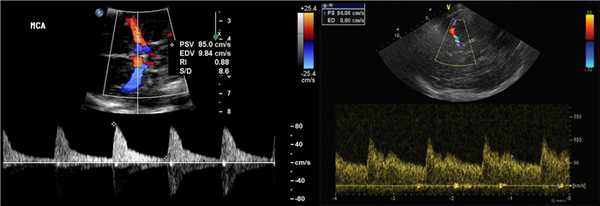

СМА красная, спектр выше базовой линии, так как поток направлен к датчику, TAMX 122 см / с. Передняя мозговая артерия сегмента A1 синяя, спектр ниже базовой линии, поскольку поток от датчика направлен к средней линии мозга.

Наиболее часто используют среднюю по времени максимальную скорость (TAMX), также называемое средней скоростью. Пиковая систолическая скорость (VS) и конечная диастолическая скорость (VD) также могут быть измерены.

При локальном сужение артерии или спазме TAMX повышается в сегменте 5-10 мм на 30 см/с по сравнению с противной стороной.

Высокий TAMX при стенозе, спазме сосудов, гипердинамическом потоке, пониженном гематокрите; низкий TAMX при артериальной гипотензии, смерти ствола мозга.

Таблица. Средняя по времени максимальная скорость (TAMX) в сосудах основания мозга (Aaslid, 1982)